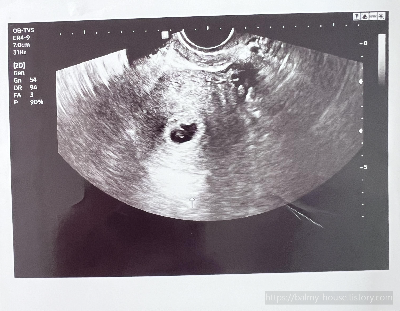

임신 5주 차 (5 Week)

1월 3일

아기집과 자궁 내 임신낭 확인(난황)

아기집 확인을 위한 초음파 검사에서 자궁 내 작은 난황이 확인되었다.

이 작은 난황은 아기의 영양주머니로 처음에는 아기를 둘러싸고 있다가 아기의 양분으로 사라진다고 한다.

다른 병원은 어떨지 모르겠지만, 현 병원의 담당 선생님께서는 난황이 확인되자 임신확인서도 함께 발급해 주셨다.